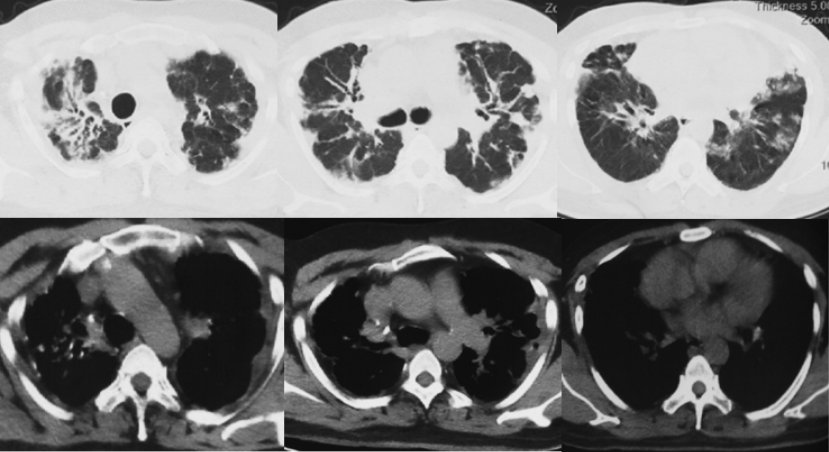

诊断“间质性肺炎,慢阻肺急性加重期,支气管扩张,Ⅱ型呼吸衰竭”。抗感染20 d,激素治疗20 d(图9),鼻导管氧疗及NPPV。咳嗽、喘息明显减轻。胸部CT:对比10月26日,双肺斑片影、磨玻璃影明显吸收(图10)。11月17日评估病情好转出院,出院后继续口服甲泼尼龙12 mg qd(11月17-30日,13 d后自行停药)。

治疗调整(2021年12月4-19日):12月4日(停激素4 d)患者自觉喘息较前加重,再次就诊于当地市医院门诊,胸部增强CT:双肺斑片影较11月9日略吸收,双侧胸膜增厚如前(图11)。12月4日加用环磷酰胺50 mg qd至12月17日患者自行停用,并再次应用甲强龙24 mg qd,于12月18日减量至12 mg qd(图12)。

第5次住院(2021年12月20-24日):12月20日(甲强龙12 mg维持治疗中)受凉后再次出现咳喘加重,伴发热,体温38.0℃,伴肌肉、关节酸痛,流清涕,于当地市医院住院。血常规:WBC 11.46×109/L(↑),NEU 8.47×109/L,LYM 1.07×109/L,血红蛋白168 g/L,血小板327×109/L。血气分析(FiO2 0.41):pH 7.40,PaO2 115.5 mmHg,PaCO2 60.5 mmHg(↑),PFR 280 mmHg(↓),HCO3- 36.2 mmol/L。12月20日胸部CT:双肺新发散在淡薄渗出斑片影,部分结节影,较12月4日加重(图13)。予比阿培南、依替米星、莫西沙星抗感染治疗(图14),患者体温恢复正常,咳喘无改善,于12月24日转至我院。

2021年12月27日胸部CT:双肺弥漫网格影、斑片影及结节影,双侧胸膜增厚,双肺间质性肺炎可能,双侧胸膜增厚,双侧少许胸腔积液(图16)。

超声引导下经皮肺穿刺(2021年12月28日):右上肺尖部胸膜及肺组织低回声处进行穿刺,穿取组织条3小条。结合影像学、组织学及特殊染色,符合PPFE,合并较多碳末沉积,局灶淋巴细胞聚集;免疫组化结果:CK(AE1/AE3)(+),KP-1(+),LCA(+),CK5/6(+),TTF-1(+);特殊染色结果:Masson(局灶+),PAS(-),弹力纤维(++),铁染色(-),银染(-)。2021年12月26日至2022年1月1日:头孢哌酮舒巴坦3 g q8h ivgtt。2021年12月27-31日:甲强龙40 mg qd ivgtt。2022年1月1日至2022年1月7日:泼尼松20 mg qd po。